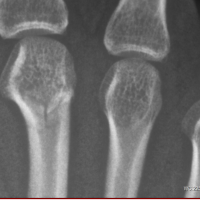

Fractura metacarpio dedo medio

respondió: Efectivamente se aprecia una fisura, si puedes quitarte esa férula y para recuperar lo antes posible la zona y bajar la hinchazón, realiza baños de contrate con 10 m de agua fría, 20 de agua caliente y acaba con 10 m en agua fría, eso hará que se...